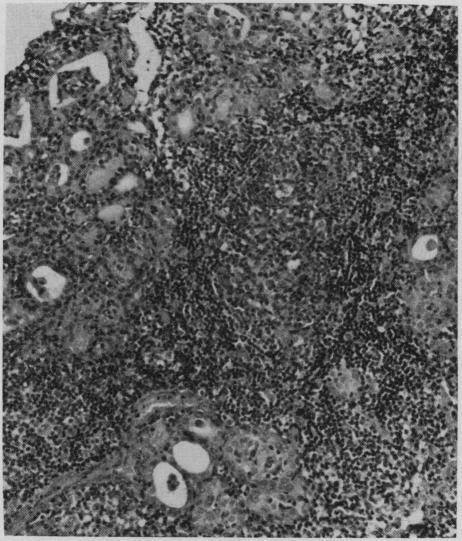

Chronic lymphocytic thyroiditis in a 5-year-old girl.

Can Med Assoc J. 1968 Nov 30;99(21):1030-7.